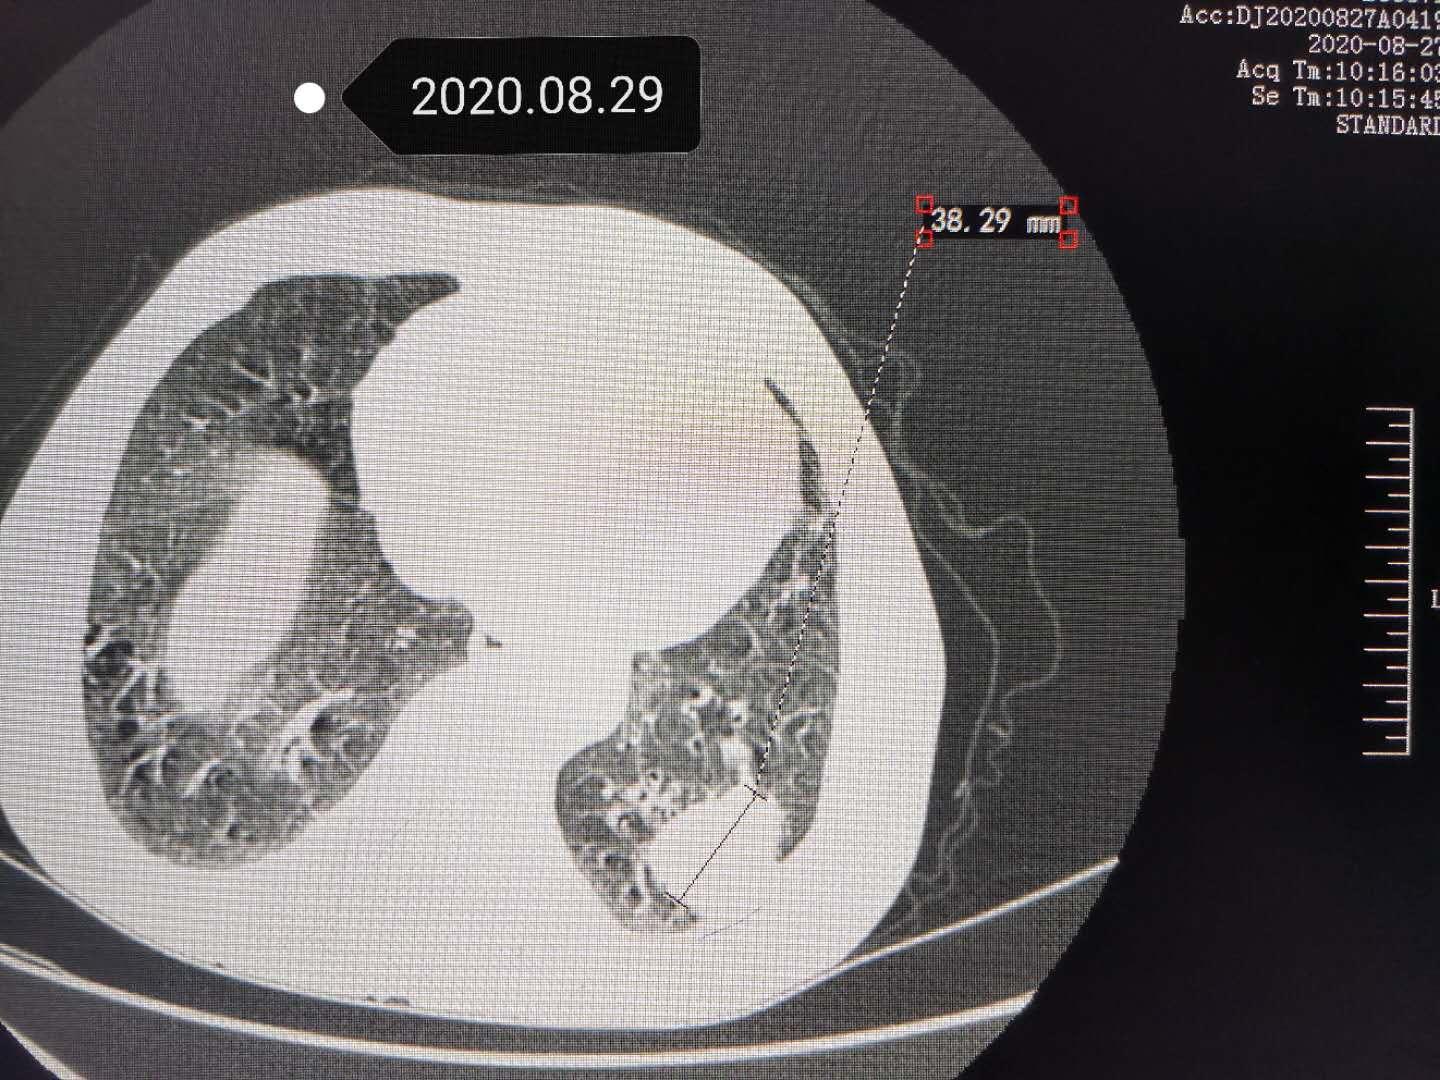

四个月后复查,肿瘤明显缩小,胸部疼痛消失

三个月过去了,老爷子来医院复查CT扫描,发现原来病变已经明显缩小,主要是肿瘤边界很清晰光滑了,说明已经没有活性,处于萎缩吸收阶段了。最大的收获是老爷子胸部不疼了。